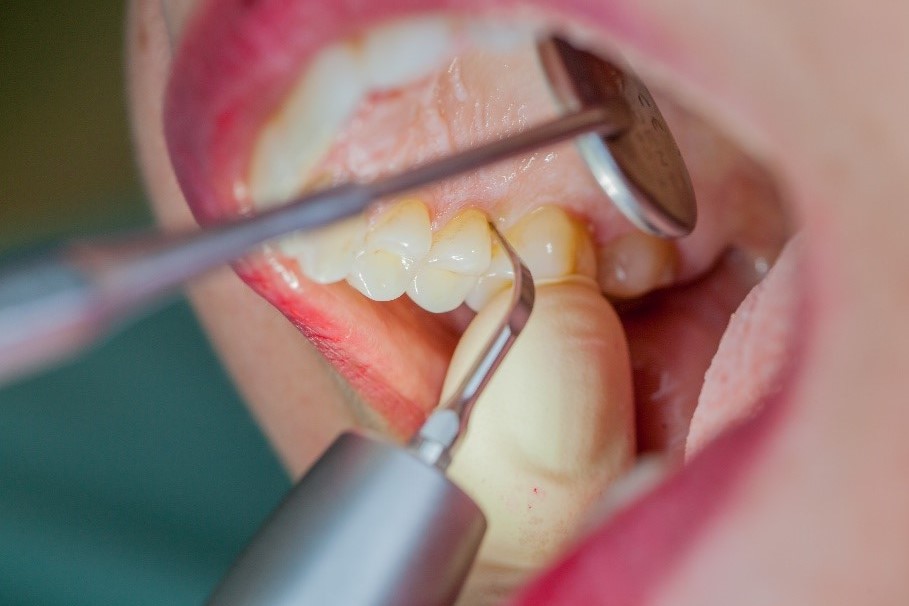

In the periodontal aftercare subsequent to implantation, soft (biofilm) and hard coatings are regularly professionally and mechanically removed.[16, 17] In the subgingival and supragingival areas, ultrasonic devices are generally used for this (Fig. 4), in combination with manual instruments where necessary. Alternatively, subgingival air polishing can be used in combination with periodontal attachments and powders.[18]

Ultrasound devices are particularly suitable for UPT

Fig. 4: Ultrasound devices are particularly suitable for UPT, for example in combination with periodontal tips (W&H Tigon+ with 1P tip)